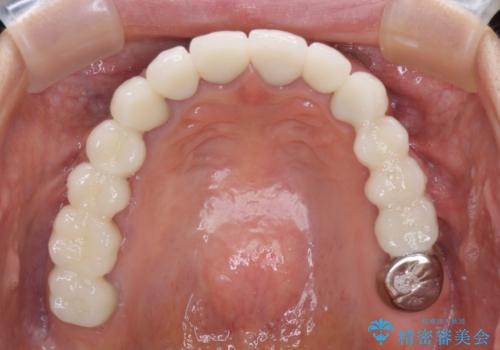

- 以前治療した歯が欠けたり、痛みを感じたりしているとのことで来院された患者様です。

アメリカ国内を転々としながら治療を行ったため治療跡がモザイク様で、クラウンが壊れていたり、抜歯が必要であったりしていました。

上下左右すべての奥歯に処置が必要であり、同時に行うと食事が取りにくくなってしまったり、手前の歯に負担がかかって初診時よりも状況が悪化したりする可能性があるため、片方ずつ処置を進めて行くこととしました。

下顎右側は骨造成を併用してインプラント治療を行い、その他の奥歯もインプラントや歯周外科処置を併用して補綴治療を進め、最後に前歯部の欠けてしまったセラミッククラウンを作り替えることとしました。